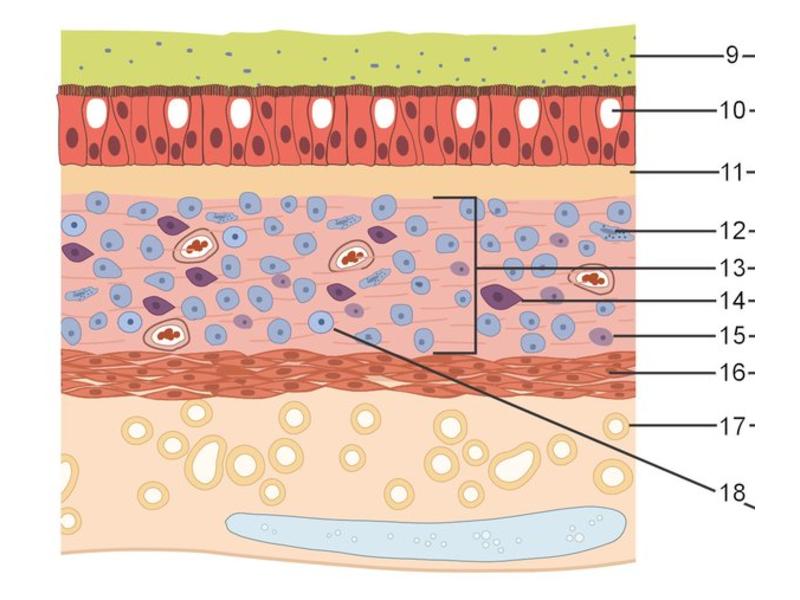

Trachea

Bronchi - Transitions

- Intrapulmonary bronchi

- Irregular cartilage

- Respiratory epithelium

- Glands

- Bronchioles

- Smooth muscle REPLACE cartilage

- Ciliated columnar > Ciliated cuboidal

- NO glands - goblet cells -> secretory cells

Clara cells